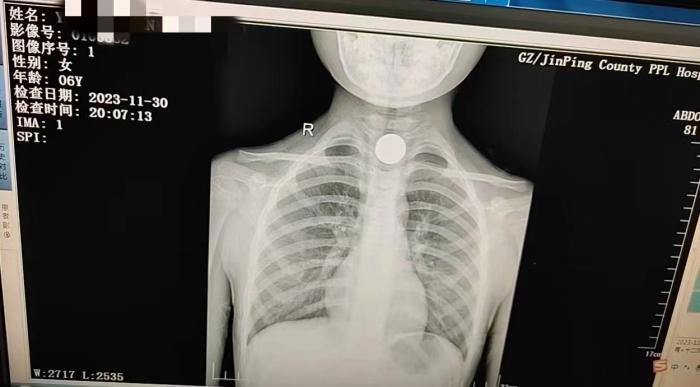

11月30日19时30分左右,锦屏县人民医院急诊收治一名误食异物患儿。经急诊查胸片拍摄结果显示硬币在食道上段,当时异物已嵌顿患儿食道约半个小时,长时间嵌顿,可能造成食管瘘,甚至引发严重并发症,有急诊手术指征,考虑患儿年龄小,清醒状态下不能配合诊疗,立即通知胃镜室、麻醉科进行评估拟定全身麻醉下行内镜下取异物。